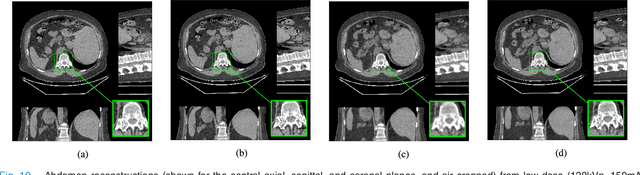

Abstract:The development of computed tomography (CT) image reconstruction methods that significantly reduce patient radiation exposure while maintaining high image quality is an important area of research in low-dose CT (LDCT) imaging. We propose a new penalized weighted least squares (PWLS) reconstruction method that exploits regularization based on an efficient Union of Learned TRAnsforms (PWLS-ULTRA). The union of square transforms is pre-learned from numerous image patches extracted from a dataset of CT images or volumes. The proposed PWLS-based cost function is optimized by alternating between a CT image reconstruction step, and a sparse coding and clustering step. The CT image reconstruction step is accelerated by a relaxed linearized augmented Lagrangian method with ordered-subsets that reduces the number of forward and back projections. Simulations with 2-D and 3-D axial CT scans of the extended cardiac-torso phantom and 3D helical chest and abdomen scans show that for both normal-dose and low-dose levels, the proposed method significantly improves the quality of reconstructed images compared to PWLS reconstruction with a nonadaptive edge-preserving regularizer (PWLS-EP). PWLS with regularization based on a union of learned transforms leads to better image reconstructions than using a single learned square transform. We also incorporate patch-based weights in PWLS-ULTRA that enhance image quality and help improve image resolution uniformity. The proposed approach achieves comparable or better image quality compared to learned overcomplete synthesis dictionaries, but importantly, is much faster (computationally more efficient).